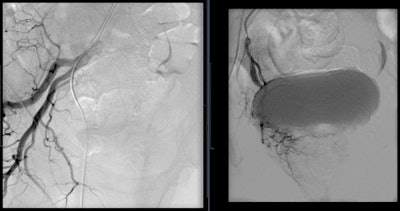

Angiogram of the left internal iliac artery showing the origin of the left prostatic artery and then very selective catheterization of the left prostatic artery by microcatheter.

Angiogram of the right internal iliac artery showing the origin of the right prostatic artery and then very selective catheterization of the right prostatic artery by microcatheter.How the treatment works